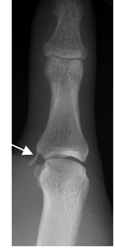

Fig 62 A. Lesión de ligamento colateral.

Rx AP. Fragmento óseo en la parte medial sobre la base de la falange media, por avulsión del ligamento colateral.